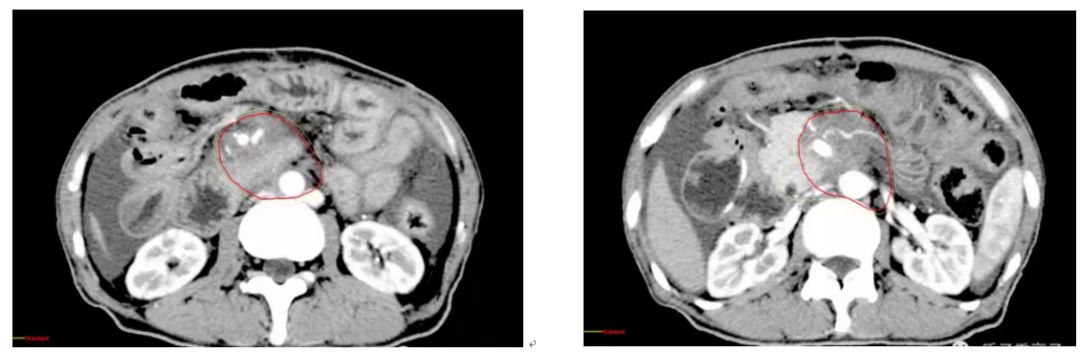

CT检查显示:胰头钩突部增大,边缘不规则毛糙,密度尚均匀,胆总管明显向后方受压,增强扫描件周围血管密集,腹膜后及胰体后方见多个结节样软组织密度影,部分已融合,轻度强化,腹膜肠间隙,胃底后方,肝脏及脾脏周围均见水样密度影

质子治疗前图像:肿瘤位于腹主动脉旁,密度不均